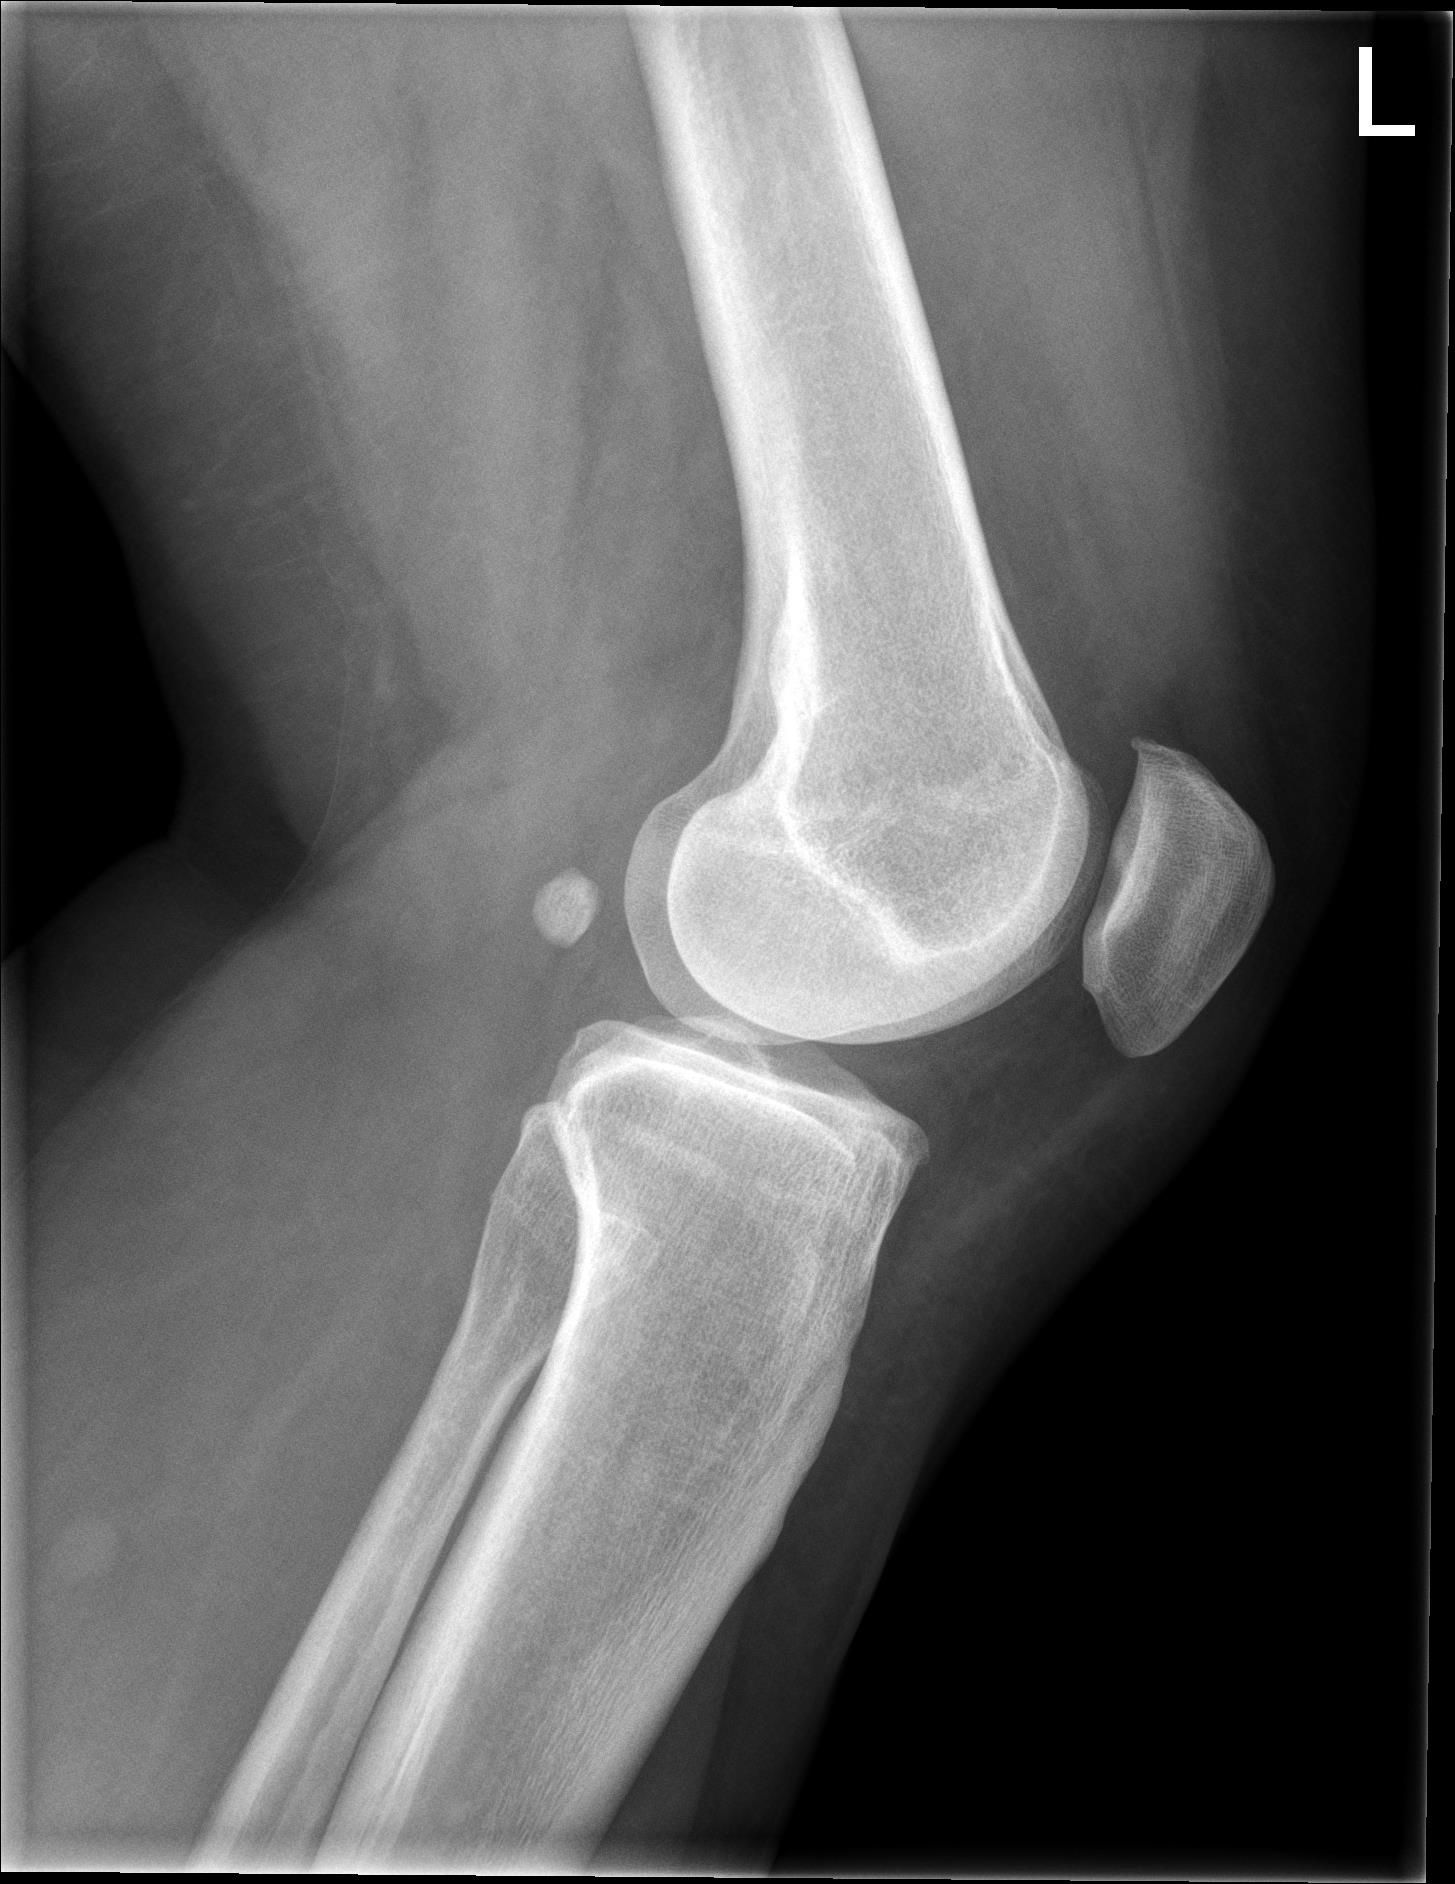

Patient A 53-year-old female patient presented at the emergency department with a locked left knee. The locking occurred whilst sitting in a chair in a flexed knee position. She was unable to unlock her knee due to the pain. On examination the knee was swollen and locked in a 70° flexion angle. An X-ray of the knee showed an inferior patellar dislocation without fractures (figure 1). Six years earlier she was treated with a medial open wedge HTO (OWHTO) with a proximal tuberosity osteotomy with a locked plate for valgus correction of medial compartment osteoarthritis. During surgery a planned 9° correction was performed. Insall-Salvati ratio (ISR) pre-operatively was 0.89. Directly after surgery ISR was 0.83 (figure 2, figure 3). Her postoperative course was uneventful, and the final results were excellent until her recent presentation.

Outcome At five months follow-up the patient did not have a new inferior patellar dislocation. She was back to her previous level of activities. The insecurities and concerns following the dislocation were diminishing. Relevant literature Inferior patellar dislocation is a rare finding only described in case reports. Two types can be found.8 The first, mostly in adolescent males, occurs after a direct blow to the flexed knee, which forces the superior pole of the patella into the notch. The quadriceps tendon is partially peeled off the anterior patellar surface. It can be treated non-operatively with a closed reduction and immobilisation of the limb in extension. The second type of inferior patellar dislocation is the degenerate type. It is caused by a hyperflexion injury in the presence of marginal patellar osteophytes. In contrast to the adolescent type, the extensor mechanism remains firmly attached. Unlocking is performed by flexing the knee. Surgical exploration is unnecessary. Early mobilisation is recommended. Patella infera is considered to be present when de ISR is <0.8.4 Patella infera is a common finding after medial OWHTO. In this case postoperatively a decrease of the ISR from 0.89 to 0.83 was measured. However, at six years follow-up it had progressively decreased to an ISR of 0.74. This late effect of surgery is only hypothetically addressed in the literature. It is possibly caused by contracture of the patellar ligament due to arthrofibrosis or scarring in this region. Excessive new bone formation during healing of the osteotomy might cause contracture of the patellar tendon.4 We believe the infrapatellar fat pad of Hoffa is also of importance in the late onset patella infera. Injury to this fat pad by direct damage or secondary to hematoma formation from a proximal tuberosity osteotomy might lead to late onset patella infera. The measurements in this report are possibly erroneous due to the X-ray at the final follow-up not being a perfect lateral view, and by interobserver variability. Advice Our case can be classified as a degenerate type of inferior patellar dislocation. The combination of the patella infera and a suprapatellar osteophyte created the circumstances for the inferior patellar dislocation to occur. We think the patella infera is introduced both direct postoperative and late onset, caused by the OWHTO with proximal tuberosity osteotomy. Therefore, we would like to use this case report to advocate the use of the distal tuberosity osteotomy in OWHTO. This technique should be taken into special consideration when the patient, who is planned for a HTO, has a low ISR, is planned for a large correction of >10° and/or has a suprapatellar osteophyte.7 In case of patella alta and/or patellar instability an OWHTO with proximal tuberosity osteotomy is recommended. By decreasing the ISR the patellar height can either be normalised or the patella can be stabilised in these cases. Acknowledgements Dr. R.D.A. Gaasbeek, orthopaedic surgeon. Disclosure statement None of the authors have anything to disclose.